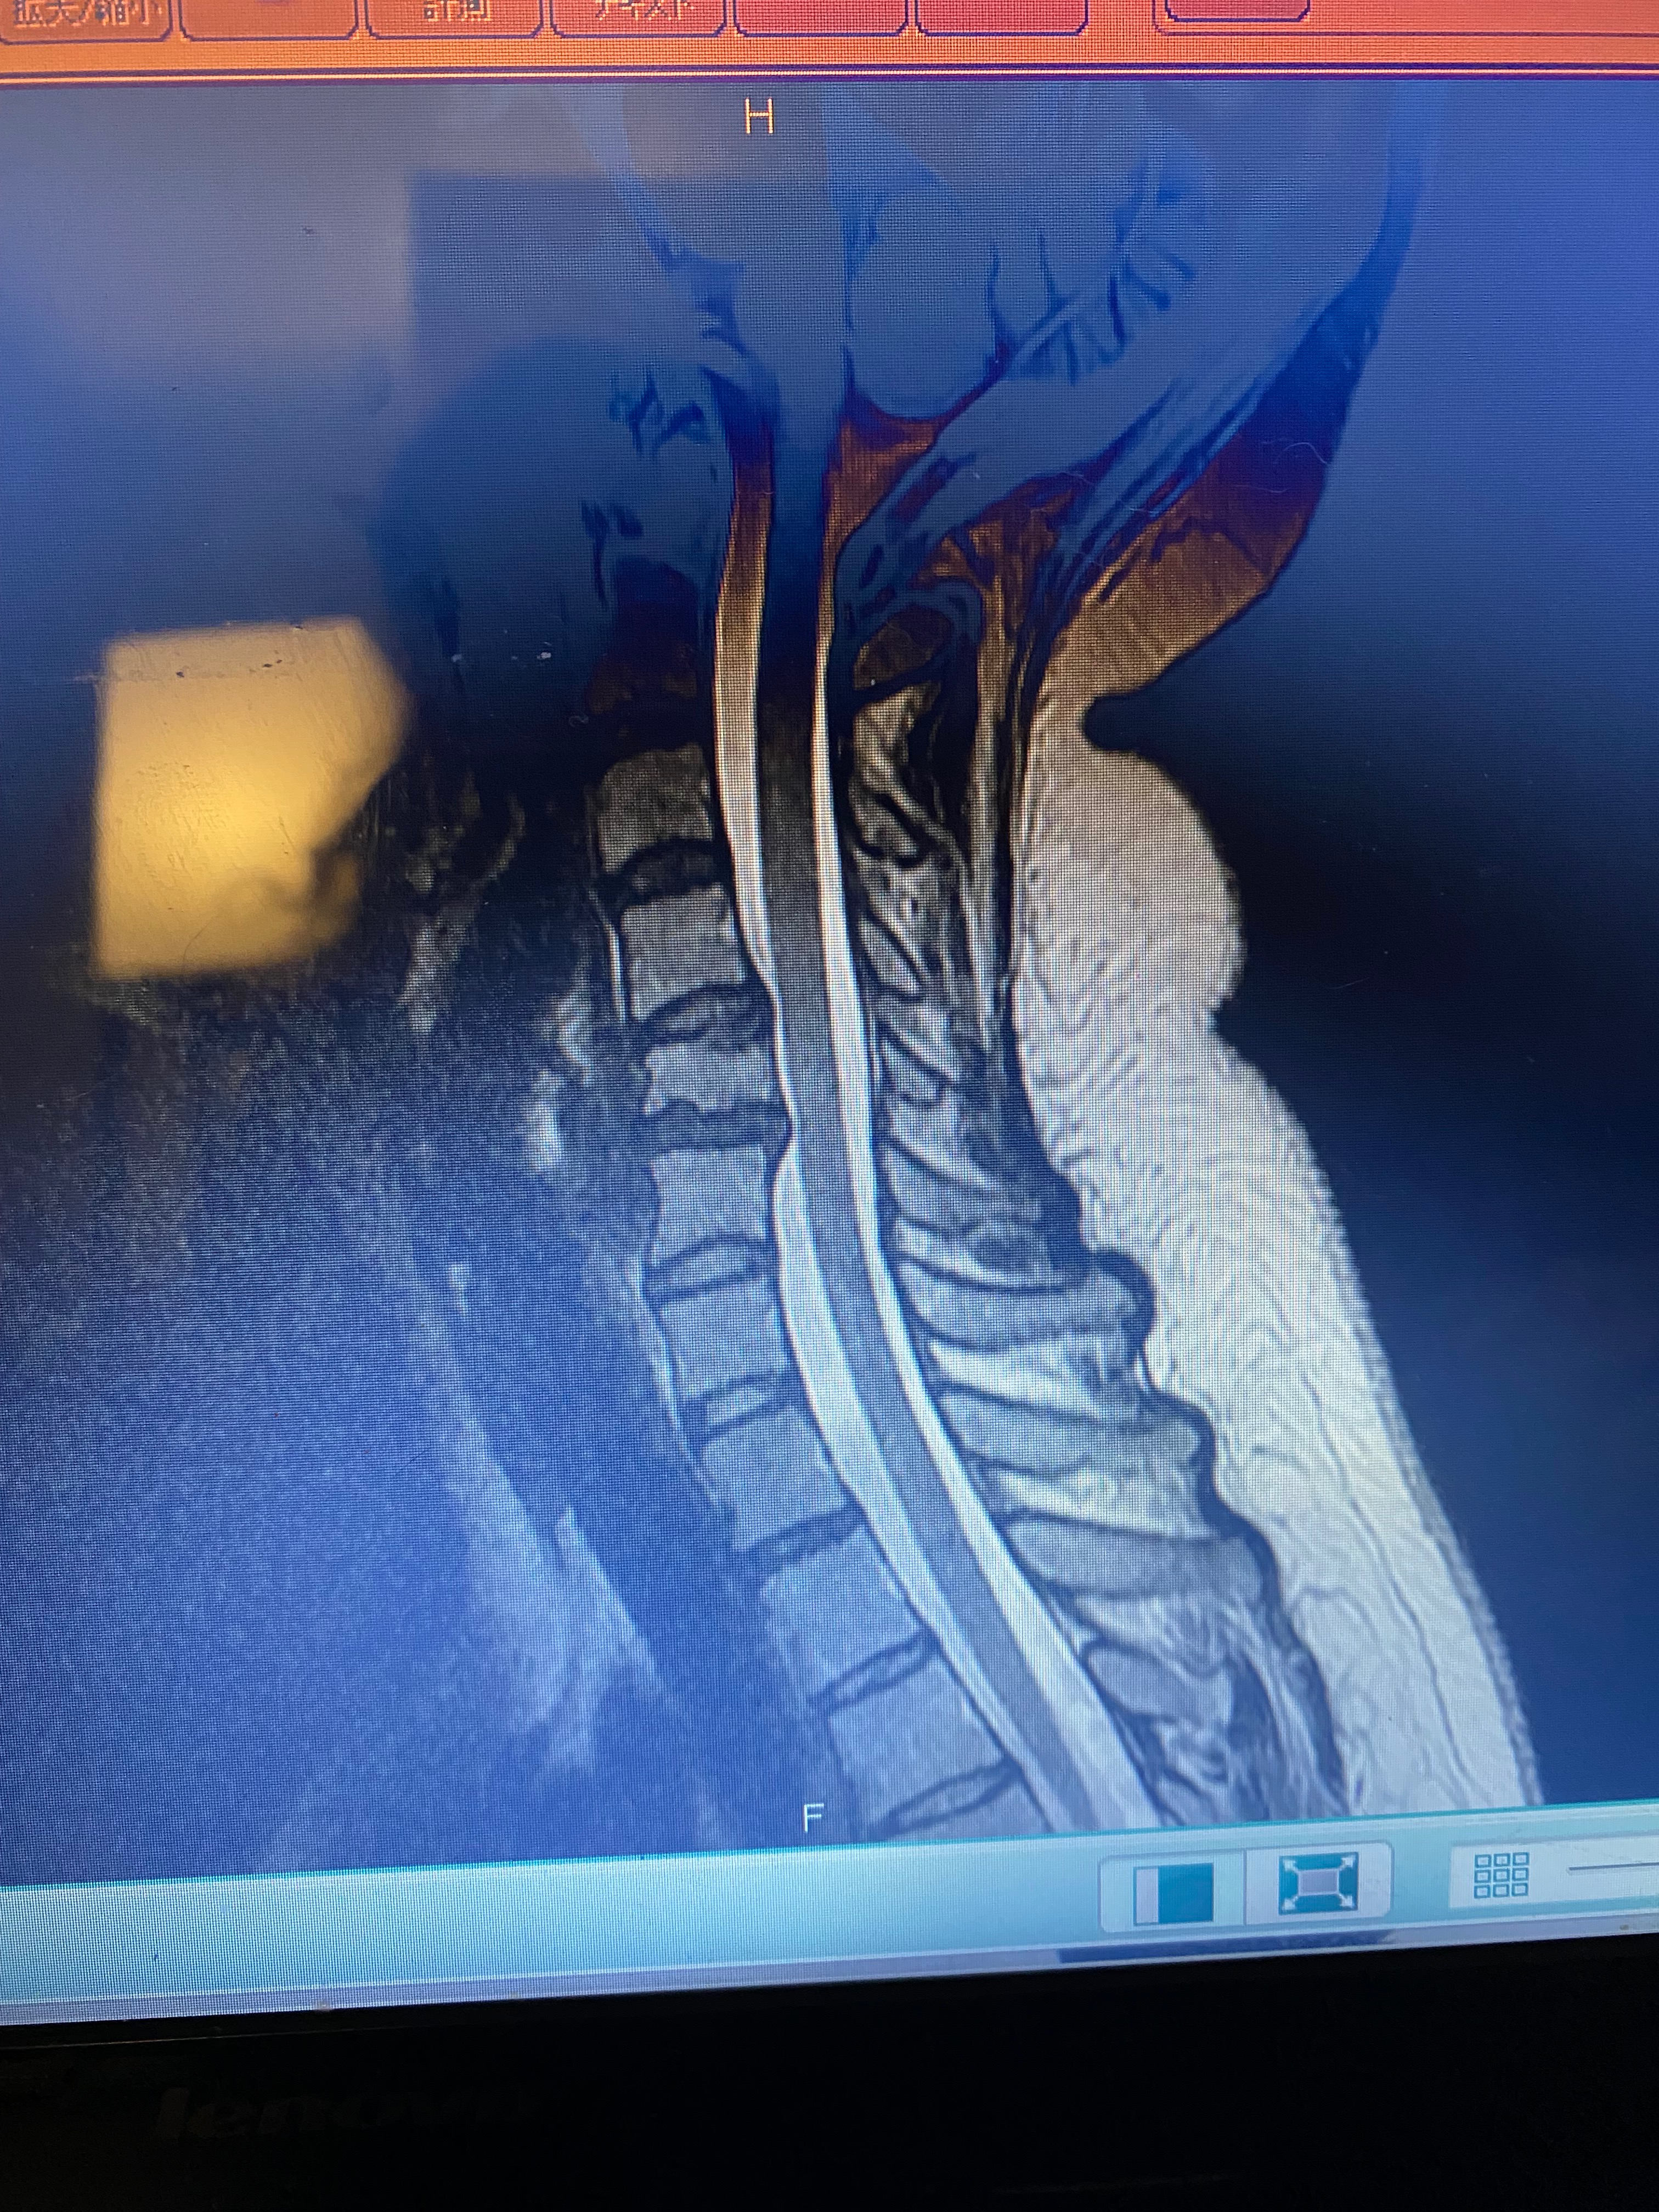

Hey all, my name is Felicia Tomolonis. This is really embarrassing, but on July 5th 2025 I was diagnosed with a concussion, which unfortunately has made my anxiety/depression/ptsd worse. It has also worsened the condition of my neck, causing more neck and nerve pain than ever before. Due to this, I’m currently out of work on short term disability. I hope to return asap and as soon as medically cleared, but with everything going on I don’t really know what else to do.

On imaging, an abdominal hernia was found that will need to be surgically repaired. It’s currently causing pain when I breathe, so working right now just seems impossible. I want to work and go back asap, because I truly can’t afford to not have help with only 60% of my earnings.